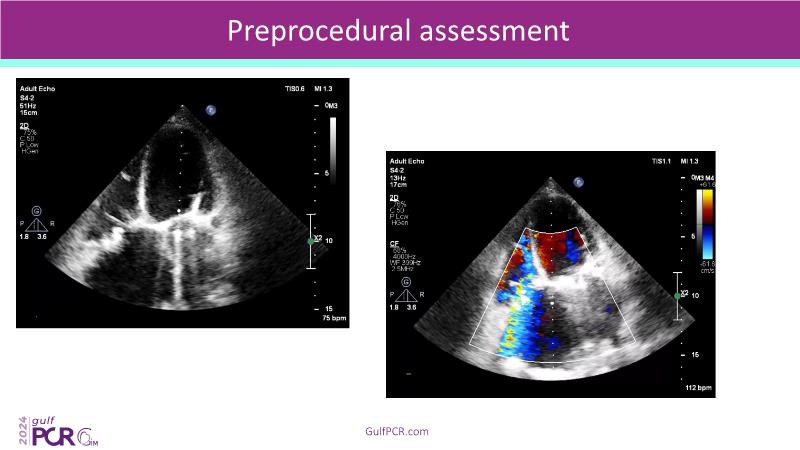

Stay ahead in TAVI innovation by exploring the advanced balloon-expandable Myval THV series. This session highlights the latest clinical data, optimal sizing and implantation techniques, and valuable real-world insights, including long-term follow-up results.

- To understand the best practices for Myval sizing and implantation technique for best outcomes